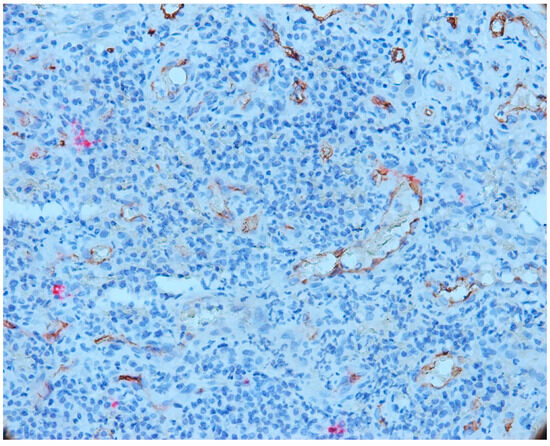

3.2. Mast Cells

3.3. Aspects of Microvessels

3.4. MCD and MVD